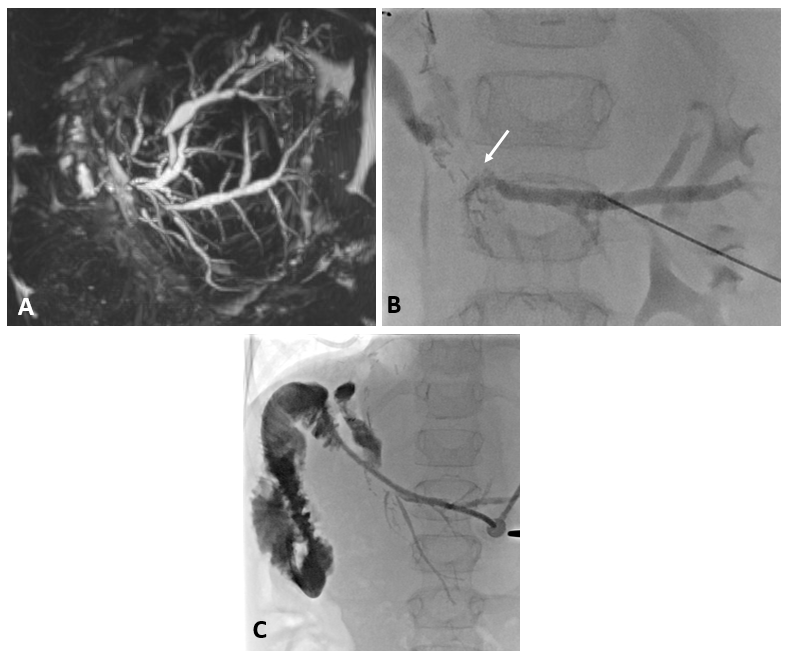

12 jähriger Junge mit Hyperplasie der der Leber

12 jähriger Junge bei dem im Rahmen der Traumadiagnostik nach einem Fahrradunfall eine fokale noduläre Hyperplasie der der Leber auffiel (A). Die weitere Diagnostik ergab den Befund einer Abernethy-Malformation Typ II mit Einmündung der Shuntvene in die linke Nierenvene (B) 3D-Rekonstruktion aus dem CT-Datensatz (PSS-portosystemscher Shunt, VCI-Vena cava inferior, VMS-Vena mesenterica superior, VRS-Vena renalis sinistra). Bei der Katheteruntersuchung (C) mit Ballonblockade der Shuntvenene (Pfeil) zeigt sich ein schmächtiges intrahepatisches Pfortadersystem. Die Druckmessung (E) unter Ballonblockade zeigte keinen signifikanten Druckanstieg. Daher konnte der interventionelle Verschluss der Shuntvene mit 2 Vascular Plugs (D) problemlos durchgeführt werden. Die Herzkatheteruntersuchung (E) zeigte allerdings bereits eine manifeste pulmonale Hypertonie mit einem pulmonalen Mitteldruck von 43 mmHg und einem Widerstands-index von 10 WE x m².

Ausgedehntes fokales Leberhämangiom eines Neugeborenen

Reifes Neugeborenes mit Hepatomegalie und Herzinsuffizienz. Das MRT der Leber (A) zeigte ein ausgedehntes kongenitales Hämangiom mit normalem Lebergewebe in den Randbereichen vor allem links. Deutlich gestaute Lebervenen (B) infolge der Rechtsherzbelastung. Die Kontrastmittelinjektion die Arteria hepatica dextra (C) zeigt mehrere arterielle Feeder mit rascher Parenchympassage. Nach interventionellem Verschluss mittels 3 Vascular Plugs und insgesamt 28 Volumen-Coils deutliche Reduktion des Shunt-Flusses im rechten Leberlappen mit noch verbleibenden Hämangiomanteilen links (D).